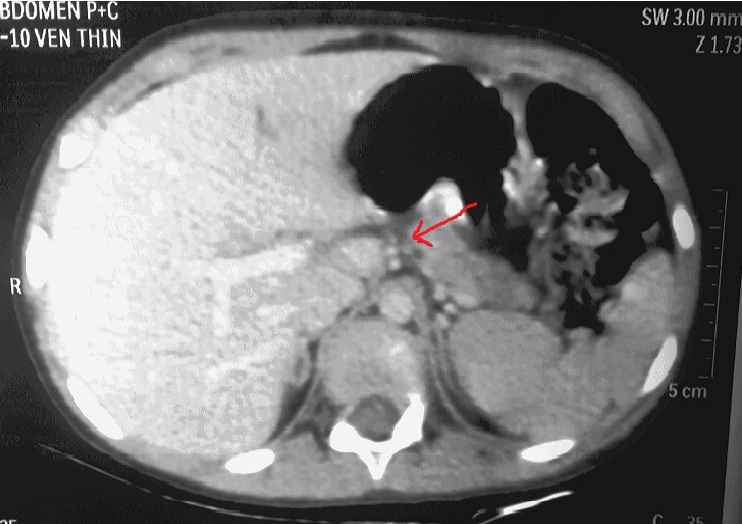

Contrast enhanced computerised tomography revealed complete transection of pancreas suspicious of ductal involvement [Table/Fig-1] which was later confirmed by MR cholangio-pancreatography [Table/Fig-2].

CT scan with arrowhead showing complete transection of pancreas with the major duct at the junction of body and neck with moderate amount of fluid in the lesser sac, anterior to the splenic vessels. Free fluid in abdomen and pelvis and bilateral mild pleural effusion also seen.